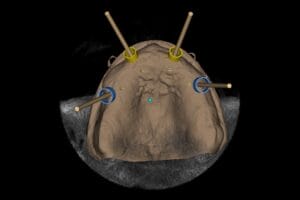

We use a CBCT (cone beam CT) scan alongside digital impressions and photography to create a precise 3D model of your mouth. This allows us to plan your implant placement virtually.

Using a 3D navigation system, our dentists position implants digitally at the perfect angle and depth. This plan is then transferred into a customised surgical guide and if needed temporary teeth, which can be placed directly onto the newly placed implants.